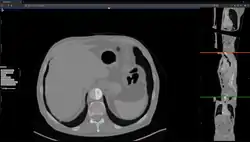

Studierfenster or StudierFenster (SF)[1][2][3] is a free, non-commercial open science client/server-based medical imaging processing online framework. It offers capabilities, like viewing medical data (computed tomography (CT), magnetic resonance imaging (MRI), etc.) in two- and three-dimensional space directly in the standard web browsers, like Google Chrome, Mozilla Firefox, Safari, and Microsoft Edge. Other functionalities are the calculation of medical metrics (dice score[4] and Hausdorff distance[5]), manual slice-by-slice outlining of structures in medical images (segmentation[6][7]), manual placing of (anatomical) landmarks in medical image data, viewing medical data in virtual reality, a facial reconstruction and registration of medical data for augmented reality,[8] one click showcases for COVID-19 and veterinary scans, and a Radiomics module.

Features

This allows client-side parsing a local folder with DICOM (Digital Imaging and Communications in Medicine)[27][28] files. Afterwards, the whole folder can be converted to compressed .nrrd (nearly raw raster data) files and downloaded as a single .zip file.

Nrrd is a library and file format for the representation and processing of n-dimensional raster data. It is intended to support scientific visualization and (medical) image processing applications.[29] With the "Dicom Browser" of Studierfenster, it is possible to select specific Studies or Series, and only convert these.

File converter

The file converter converts a medical volume file (e.g. a non-compressed .nrrd file) to a compressed/binary .nrrd file. After the conversion, the compressed .nrrd file can be downloaded and used with the "Medical 3D Viewer" for 2D and 3D visualization, and further image processing.